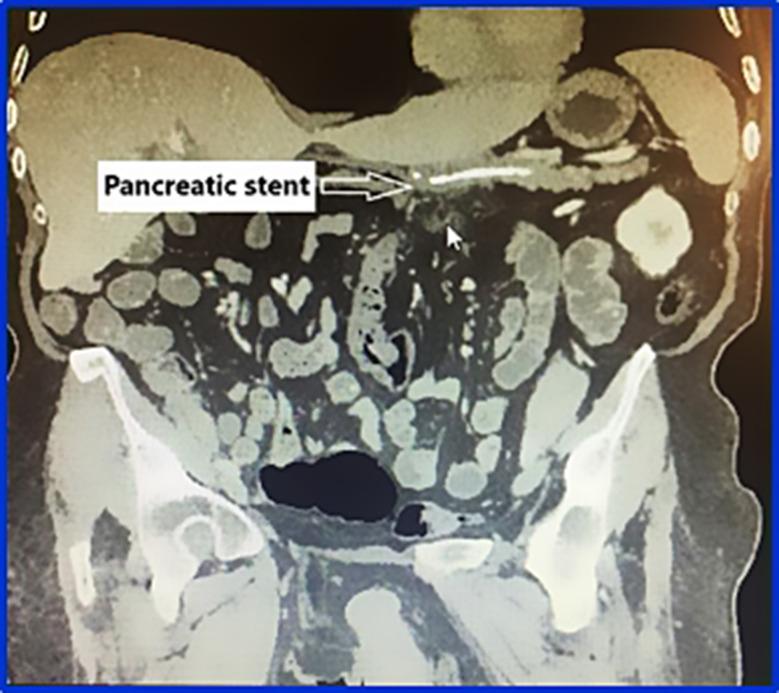

Forty-eight individuals who had pancreaticoduodenectomy procedures performed between March 2022 and March 2024 were examined. Based on the placement of a stent and omental flaps around the pancreaticojejunal anastomosis, the patients were split into two groups: group A, consisting of twenty-four patients, did not get omental wrapping and stenting, and group B, consisting of twenty-four patients, received omental wrapping with stent inside the pancreaticojejunal anastomosis. To evaluate the efficacy of the omental flap operation in preventing postoperative pancreatic fistula and other complications, perioperative data from both groups was examined.

There were no discernible variations in the clinical traits of the two groups. Group B experienced considerably lower occurrences of postoperative pancreatic fistula (20.8% vs. 4.2%), post-pancreatectomy hemorrhage (4.2% vs. 0%), biliary fistula (4.2% vs. 0%), and delayed gastric emptying (12.5% vs. 4.2%). Group B had a considerably lower overall morbidity rate (41.7% vs. 8.3%) and shorter hospital stay (15.3 vs. 10.9 days) than to group A.

Following pancreaticoduodenectomy, pancreatic stent and omental flaps around the pancreatic anastomosis can lower the risk of postoperative pancreatic fistula, post-pancrectomy bleeding, and delayed gastric emptying. This straightforward and efficient treatment can decrease the overall morbidity following pancreaticoduodenectomy.